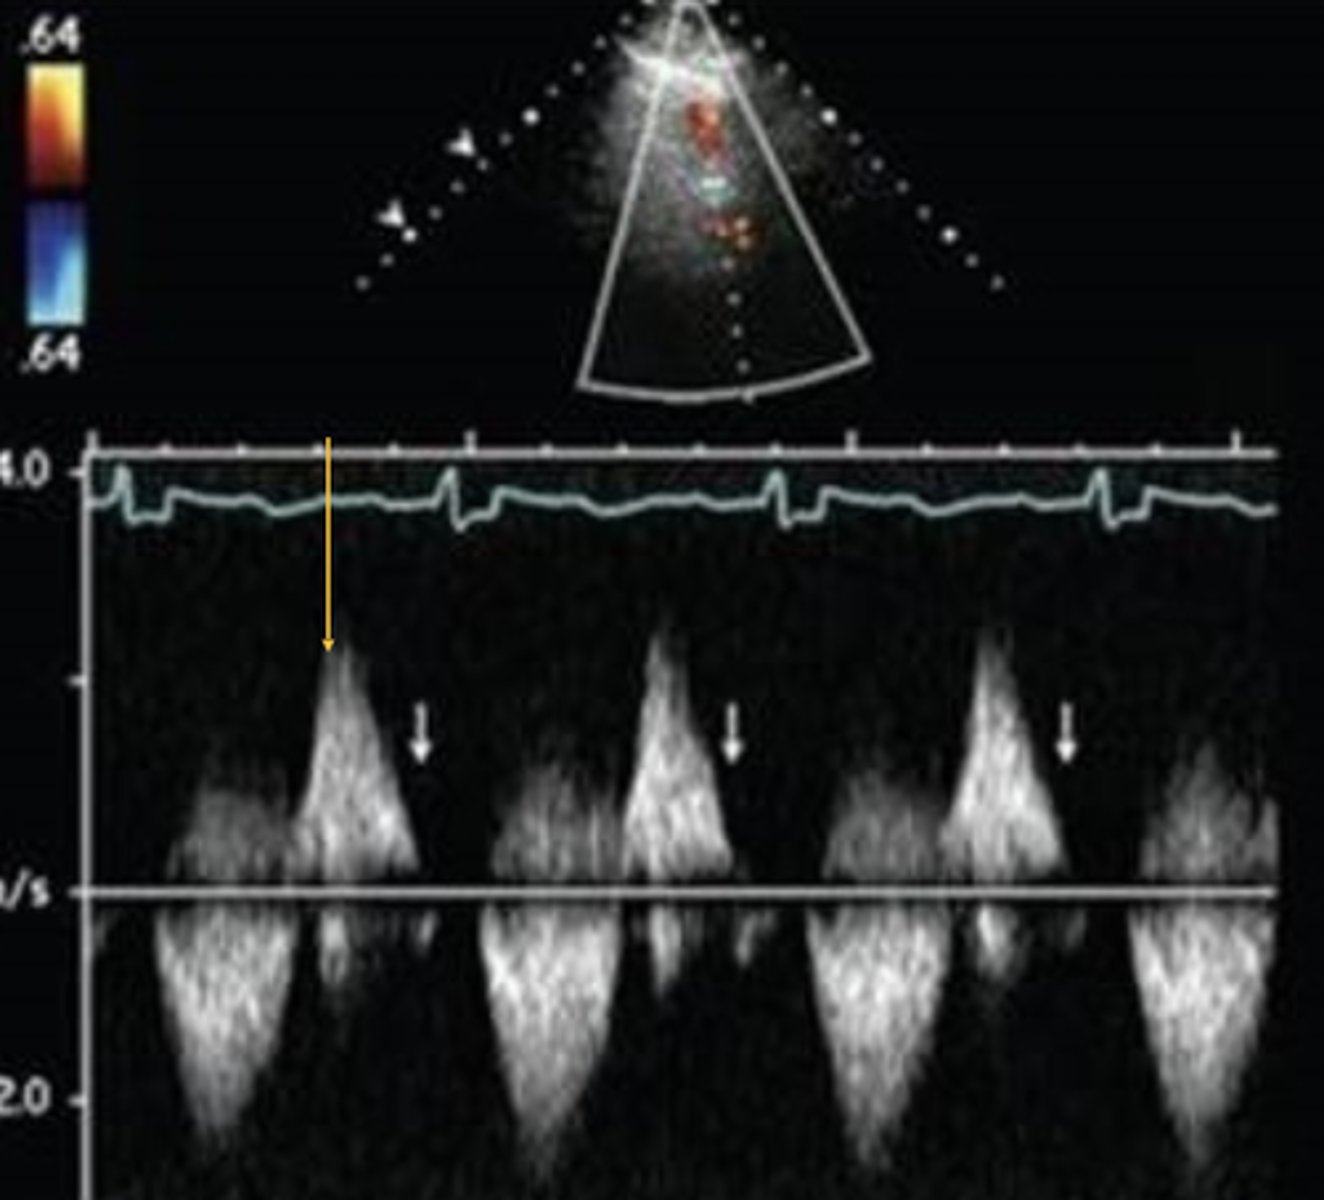

Flow Reversal in Pulmonary Artery Branches

Indicates severe PR

PR Index

Ratio of PR duration to total diastolic duration

PR Index for Severe PR

< 0.77